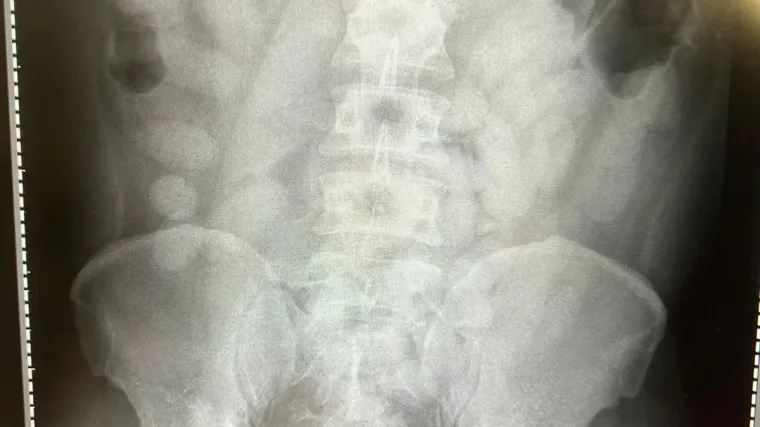

"Rendgenska snimka koju smo obavili u obližnjoj klinici, potvrdila je sumnju. Kompletan sustav želuca i crijeva kod muškarca bio je ispunjen paketićima s drogom", opisao je glasnogovornik Glavne carinske službe Köln Jens Ahland:

"Imao je u sebi 72 paketića, svaki ispunjen sa 14 grama kokaina. U tijelu je sakrivao ukupno više od jednog kilograma, što je za nas novi tužni rekord. Rizik pri ovakvom krijumčarenju droge je ogroman. Da je samo jedan paketić puknuo u njegovom tijelu, ne bi mu se moglo spasiti život."